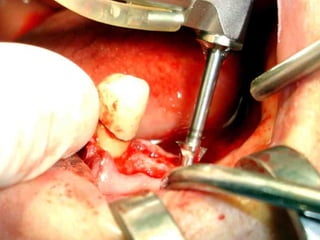

Primer tiempo quirúrgico; Exposición del maxilar para tomar una impresión del

hueso y poder elaborar la estructura implantaria.

Lingitud de hueso

Disponible 20 mm.

Implante en posición

Dejamos el implante sepultado por 4 meses previos al inicio del procedimiento

Protésico.

• Los implantes deben dejarse sin carga unLos implantes deben dejarse sin carga un

promedio aproximado de cuatro meses,promedio aproximado de cuatro meses,

después de los cuales se inicia el trabajodespués de los cuales se inicia el trabajo

protésico.protésico.

• Cuidados postoperatorios: Analgésicos,Cuidados postoperatorios: Analgésicos,